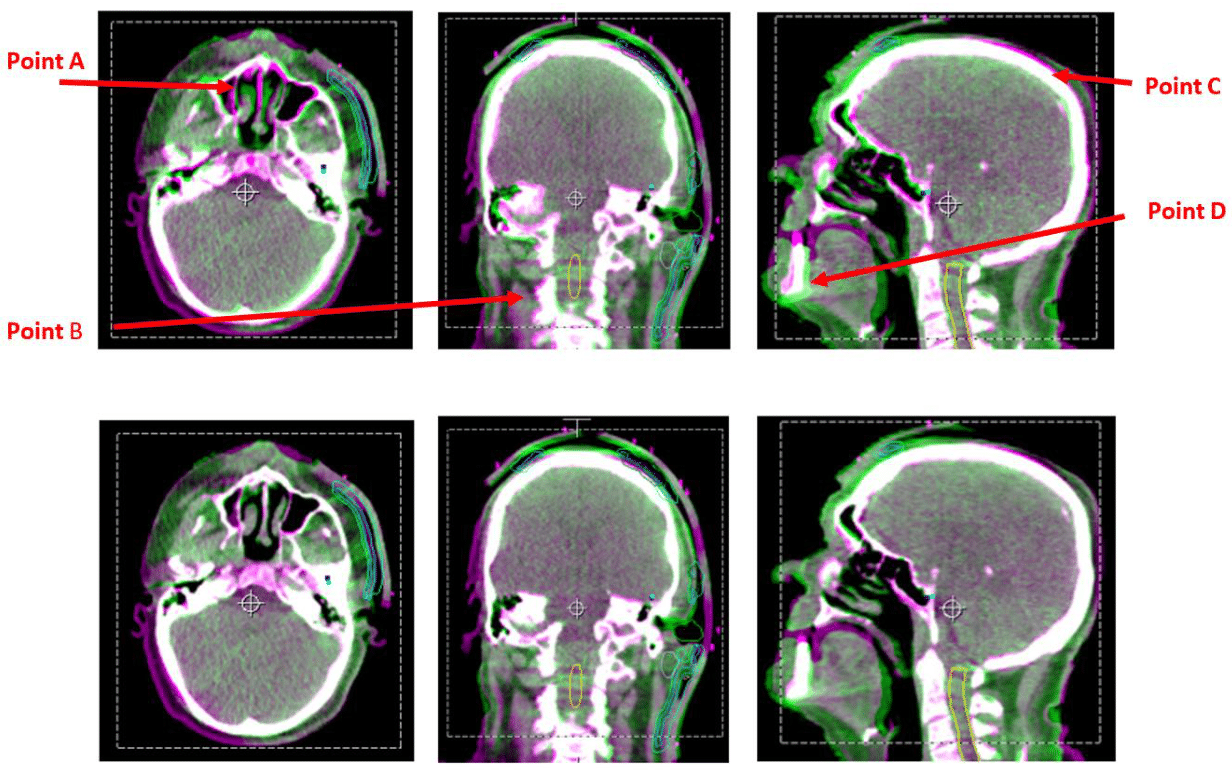

In addition to the statistical evidence, it was evident clinically, that introduction of rotation corrections in the image registration led to a better image match and anecdotally, greater satisfaction by the radiation therapist performing task. Figure 3 demonstrates the effect of introducing rotation correction in a typical head and neck case.

Figure 3 Illustrations demonstrating the impact of including rotations in the image registration – bottom row of images has both translation and rotation corrections applied (6D).

The greatest discrepancies can be seen at points A, B, C and D where the anatomy is not perfectly overlayed. From this example, introduction of rotational corrections led to superior image registration.